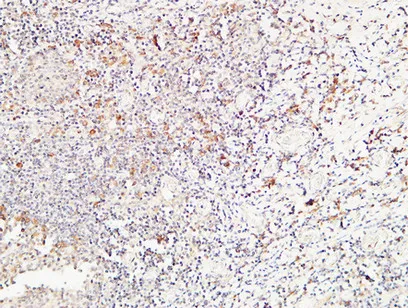

CD244 Rabbit Polyclonal Antibody

Cat: APRab08306

Size1:50μl Price1:$118

Size2:100μl Price2:$220

Size3:500μl Price3:$980

Size2:100μl Price2:$220

Size3:500μl Price3:$980